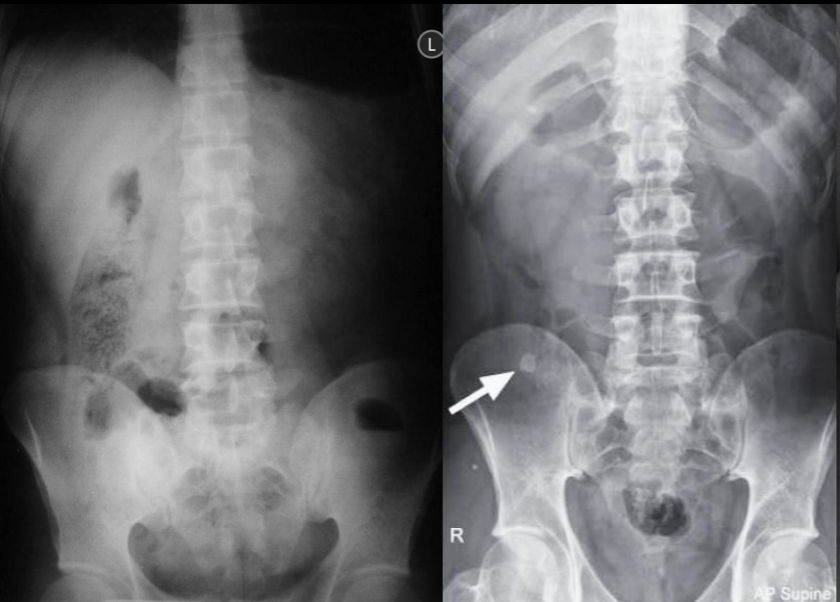

ABCDE rx

Apendicolito

Borramiento psoas

Asa centinela

Hiperdensidad sacroiliaca derecha

Escoliosis antialgica

Apendicolito y Escoliosis antialgica

Borramiento del psoas e hiperdensida articular